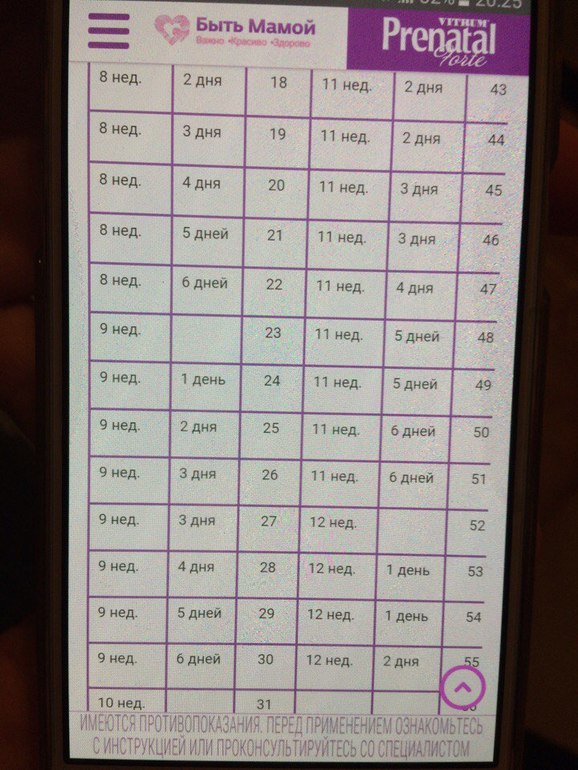

срок беременности число ударов/мин.

4-6 недель 80-85

6 недель 100-130

7 недель 130-150

8 недель 150-170

9 недель 170-190

10 недель 170-190

11 недель 140-160

12-40 неделю 140-160

У вас 7 неделек беременности по пя

Спасибо большое, то есть если по ПЯ 7 неделек, тогда сердечко медленно немного( а по КТР не вернее судить о сроке? Я уже совсем запуталась(

Ну мне почему то больше кажется что у тебя 6 неделек и сколько то дней . Если так то у тебя нет отставания

Вот смотри табличку (фото 2 скинула) если по ней то у тебя да же 6 неделек нет. Нуууу мать возможно у тебя 5-6 недель ну или что то около 6 недель как то наверно так